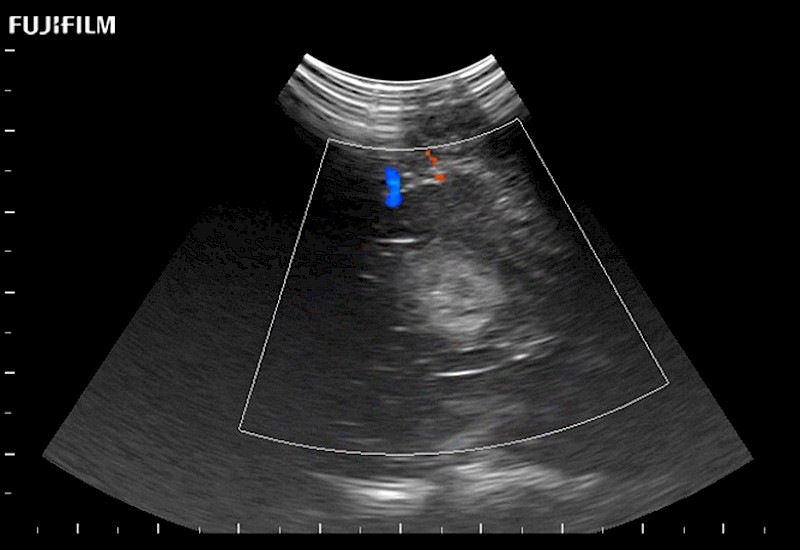

The world's only phased array burr-hole transducer that is ideal for scanning during burr-hole guidance procedures.

Main Specifications: